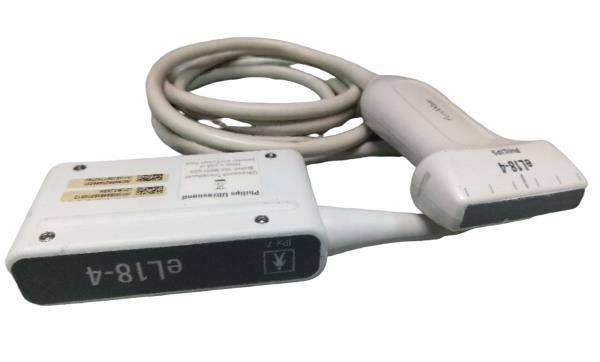

Pro Digital Laptop Ultrasound Machine Linear Array Probe + Transvaginal Probe

The included linear array probe provides high-resolution imaging, ideal for musculoskeletal, vascular, and soft tissue imaging. It delivers clear, detailed images for accurate diagnostics in various applications. The transvaginal probe is designed for internal imaging, offering clear visualization of the female reproductive organs, making it ideal for gynecological exams such as early pregnancy assessments and pelvic evaluations.